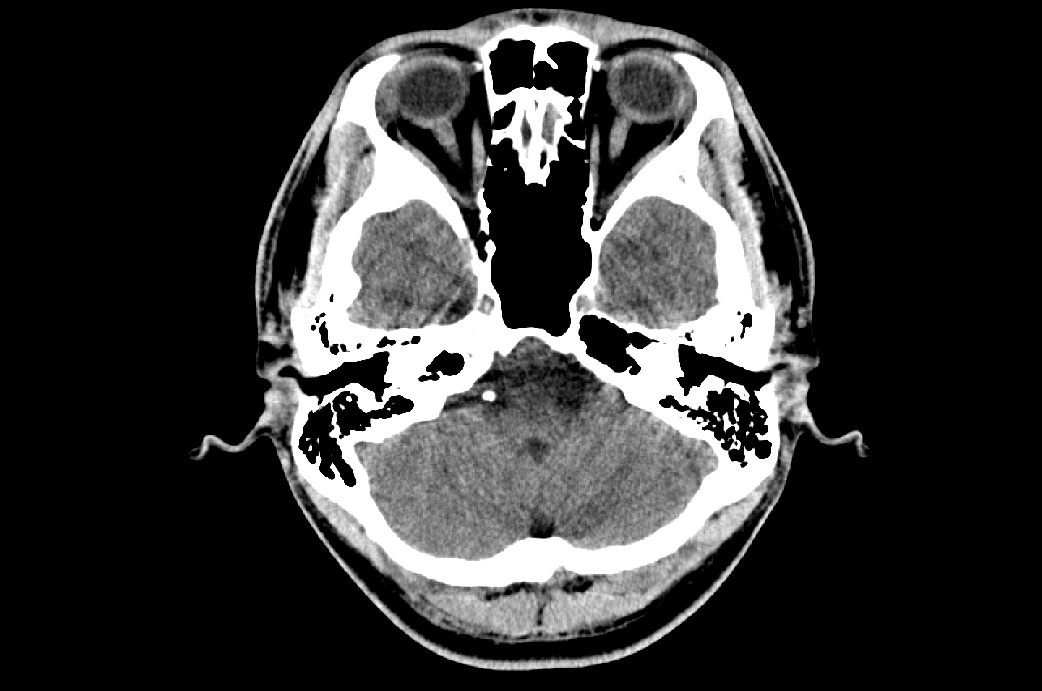

評価により脳震盪の疑いが認められた場合、評価の情報を携え速やかに脳神経外科へ受診させます。